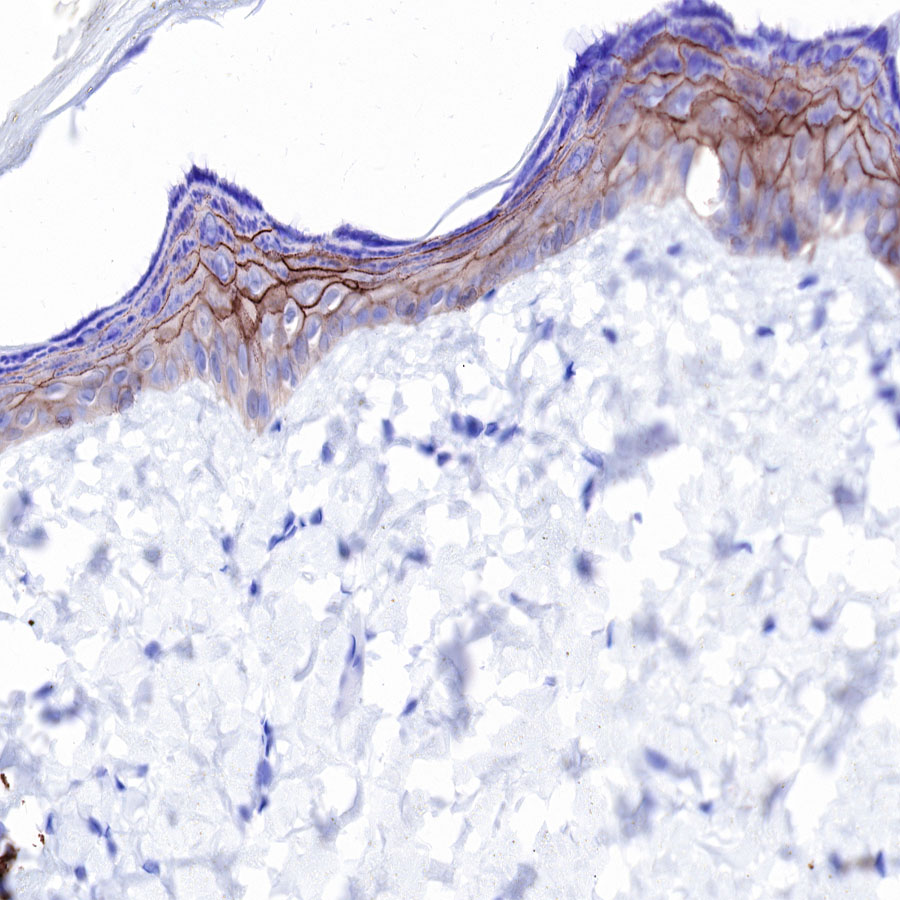

| IHC-P |

1:250 |

Claudin-1 is a protein that in humans is encoded by the CLDN1 gene.It belongs to the group of claudins.

Tight junctions represent one mode of cell-to-cell adhesion in epithelial or endothelial cell sheets, forming continuous seals around cells and serving as a physical barrier to prevent solutes and water from passing freely through the paracellular space. These junctions are composed of sets of continuous networking strands in the outwardly facing cytoplasmic leaflet, with complementary grooves in the inwardly facing extracytoplasmic leaflet. The protein encoded by this gene, a member of the claudin family, is an integral membrane protein and a component of tight junction strands. Loss of function mutations result in neonatal ichthyosis-sclerosing cholangitis syndrome.